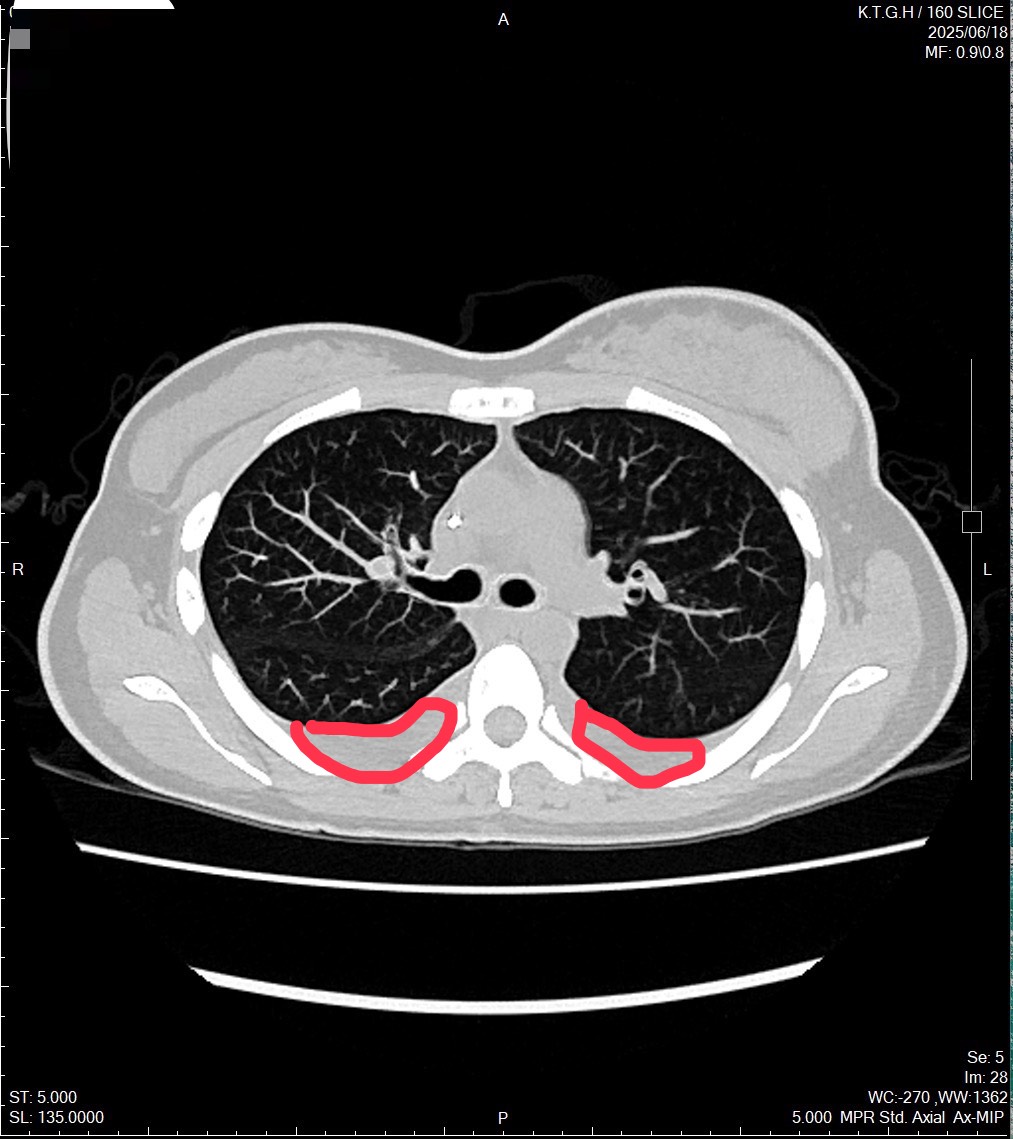

北部一位林小姐,長期輪大夜班、作息不規律,直至2023年5月在自我檢查時發現乳房有硬塊,一開始未立即就醫,直到腫塊逐漸變大,才前往醫院檢查。確診時,已罹患乳癌第四期,且癌細胞已轉移至骨骼、肺部與腹部,甚至造成雙側肺積水和呼吸困難,病情比她想像中更為嚴重。

光田綜合醫院乳房外科廖志斌醫師指出,林小姐罹患的是最常見的「管腔型乳癌」,因此,醫療團隊評估屬於內臟轉移急症,先給於化學治療,之後再採用口服標靶合併荷爾蒙藥物治療。經過一段時間,林小姐的症狀逐漸獲得控制,生活品質明顯改善。